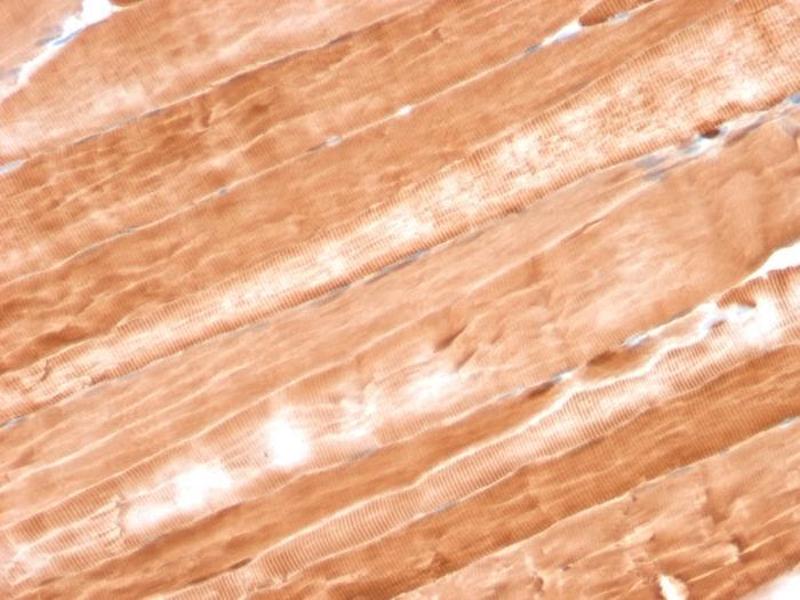

Immunohistochemistry (IHC), Staining Methods (StM)

Positive Control: SK-BR3 or T47D cells. Skeletal or Cardiac Muscle.

Known Application: Immunohistochemistry (Formalin-fixed) (1-2 μg/mL for 30 minutes at RT),(Staining of formalin-fixed tissues requires boiling tissue sections in 10 mM Citrate Buffer, pH 6.0, for 10-20 min followed by cooling at RT for 20 minutes),Optimal dilution for a specific application should be determined.

Myoglobin is a cytosolic oxygen-binding protein responsible for the storage and diffusion of oxygen within myocytes. Expression of myoglobin is highest in skeletal and cardiac muscle. Myoglobin is well accepted as an O2-storage protein in muscle, capable of releasing O2 during periods of hypoxia or anoxia.In combination with other striated muscle markers such as vimentin and myogenin, myoglobin is helpful in the identification of rhabdomyosarcoma and tumors with skeletal muscle differentiation. Reportedly, myoglobin is expressed on epithelial cancer cells due to changed metabolic and environmental conditions.